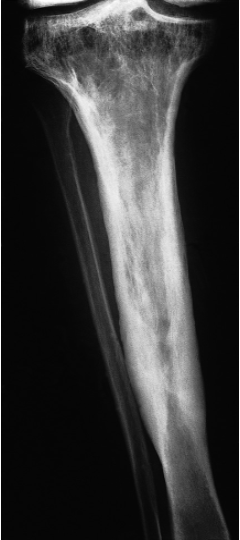

Coarse trabeculae

• in Paget’s Disease,.

• The other features of Paget’s disease thickened cortex and bone expansion ,are also present.